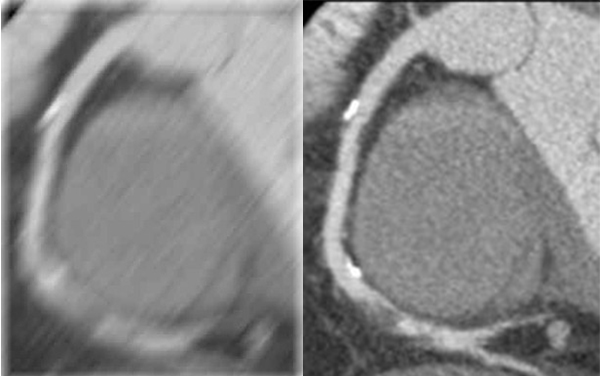

Cardiac Viewer Images

View heart images of each phase, execute three-dimensional reconstruction and heart extracted for CT heart images, and then view patient heart by more intuitive way, diagnosis various cardiovascular diseases.

• Different phases data comparison

• 4D play

• Oblique MPR display